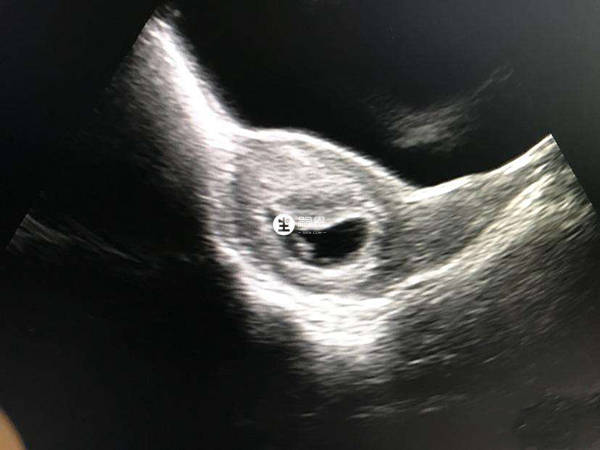

34歲頭胎懷孕,孕早期一切順利,我的雌二醇數值比較高,最近一次檢查雌二醇超過2000,在孕8周時b超檢查就已經有了胎心胎芽,我的hcg和孕酮數值也是正常的,這是不是就說明我之後就不會再面臨胎停育了?因為我聽大夫說我這個年齡懷孕很危險,要我好好保養!孕9周雌二醇超過2000有胎心胎芽表示胚胎髮育較好,但這並不代表胚胎就一定穩定了,發生胎停育的機率也是存在的。後期孕婦需要多多關注自己的hcg翻倍情況,以及孕酮數值,如果hcg翻倍不佳,同時孕酮值低於20ng/ml,那麼胎兒也是有隨時停搏的危險。只有胎盤出現後,出現胎停育的概率才會比較低,在此期間孕婦還是需要關注個人身體情況,避免危險行為。

雖然說胎停育往往發生於懷孕6-9周,在孕9周已經發現了胎心胎芽,且雌二醇數值超過了2000,那麼胎停的機率就會有所降低,但是這並不代表之後就不會再胎停,真正的穩定是需要胎盤出現。下面就為大傢俱體分析孕9周雌二醇超過2000有胎心胎芽是否還會胎停: